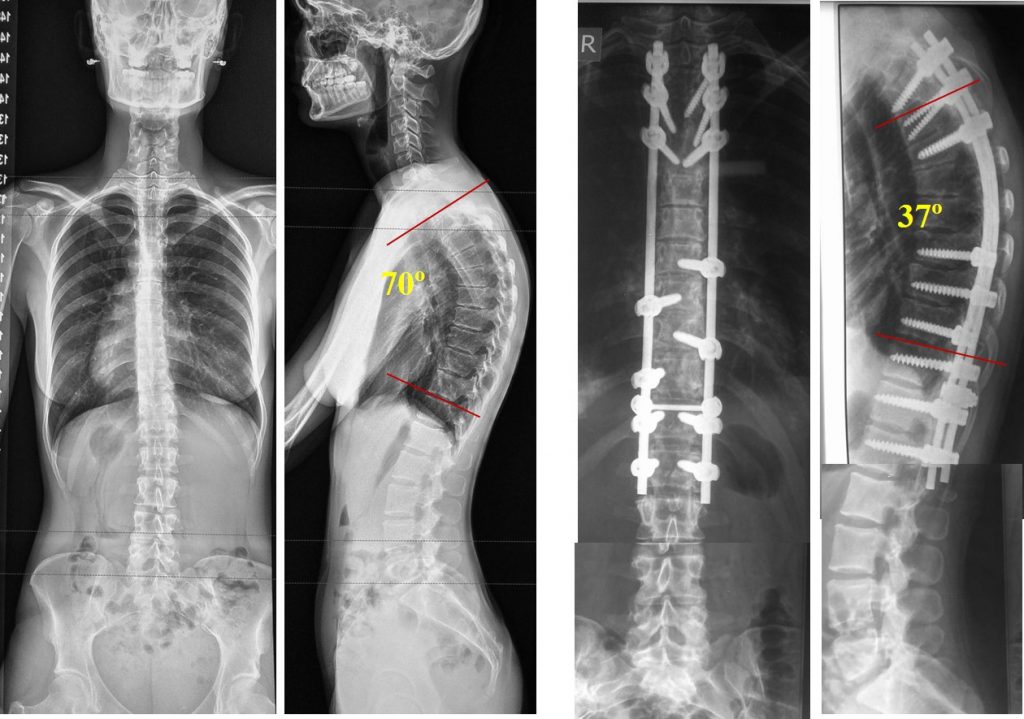

Искривление позвоночника: причины и последствия на снимках

Раздел: Визуальный дайджест